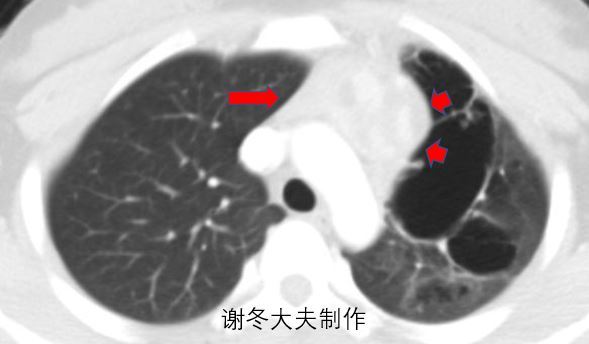

1.谢大夫,这个前纵隔占位是胸腺瘤吗?

元芳,这个不是胸腺瘤,这是一个异位的纵隔胰腺,伴有病灶破裂腐蚀左肺上叶,造成左肺上叶感染。